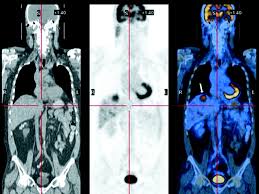

Pet ct scan prices depend on the hospital. It involves an injection with a tracer that allows us to see how organs and tissues are working. Paul's hospital is an acute care teaching and applied research hospital delivering compassionate and holistic care to the people of saskatoon and saskatchewan. An intercom in the room allows you to speak to someone at any time. The table may be hard or cold, but you can request a blanket or pillow. I am very happy for you paul that your pet scan came out with positive results. Available to ubc students and hospital employees. A pet scan causes no pain. This means you won't need to stay in hospital overnight. Inspired by the example of st. Friday, march 29th st paul pet hospital cathedral hill will be closing at 5:30pm due to staff meeting purposes. Paul pet hospital is one of the best animal hospitals in the twin cities. Compare pricing for medical facilities in st.

Paul's hospital is an acute care, teaching and research hospital located in downtown vancouver. Inquire about the latest price rates to compare price and save money. Paul's hospital is an acute care hospital located in downtown vancouver, british columbia, canada. An intercom in the room allows you to speak to someone at any time. By helping one another, we make our city a better place. A pet scan is a scan that can test for certain diseases. Hospitals with pet scan and price rates. Paul pet hospital, we live and breathe community spirit. Paul's hospital is a catholic hospital with a rich history that was founded in 1907 by the grey nuns. You will usually have been referred to paul strickland scanner centre by staff from a gp practice, nhs hospital, or an independent provider. They included whether i had hypertension, allergies to medicine, diabetes, or was claustrophobic. Imtj best international hospital of the world (awards 2017). Why the test is performed.